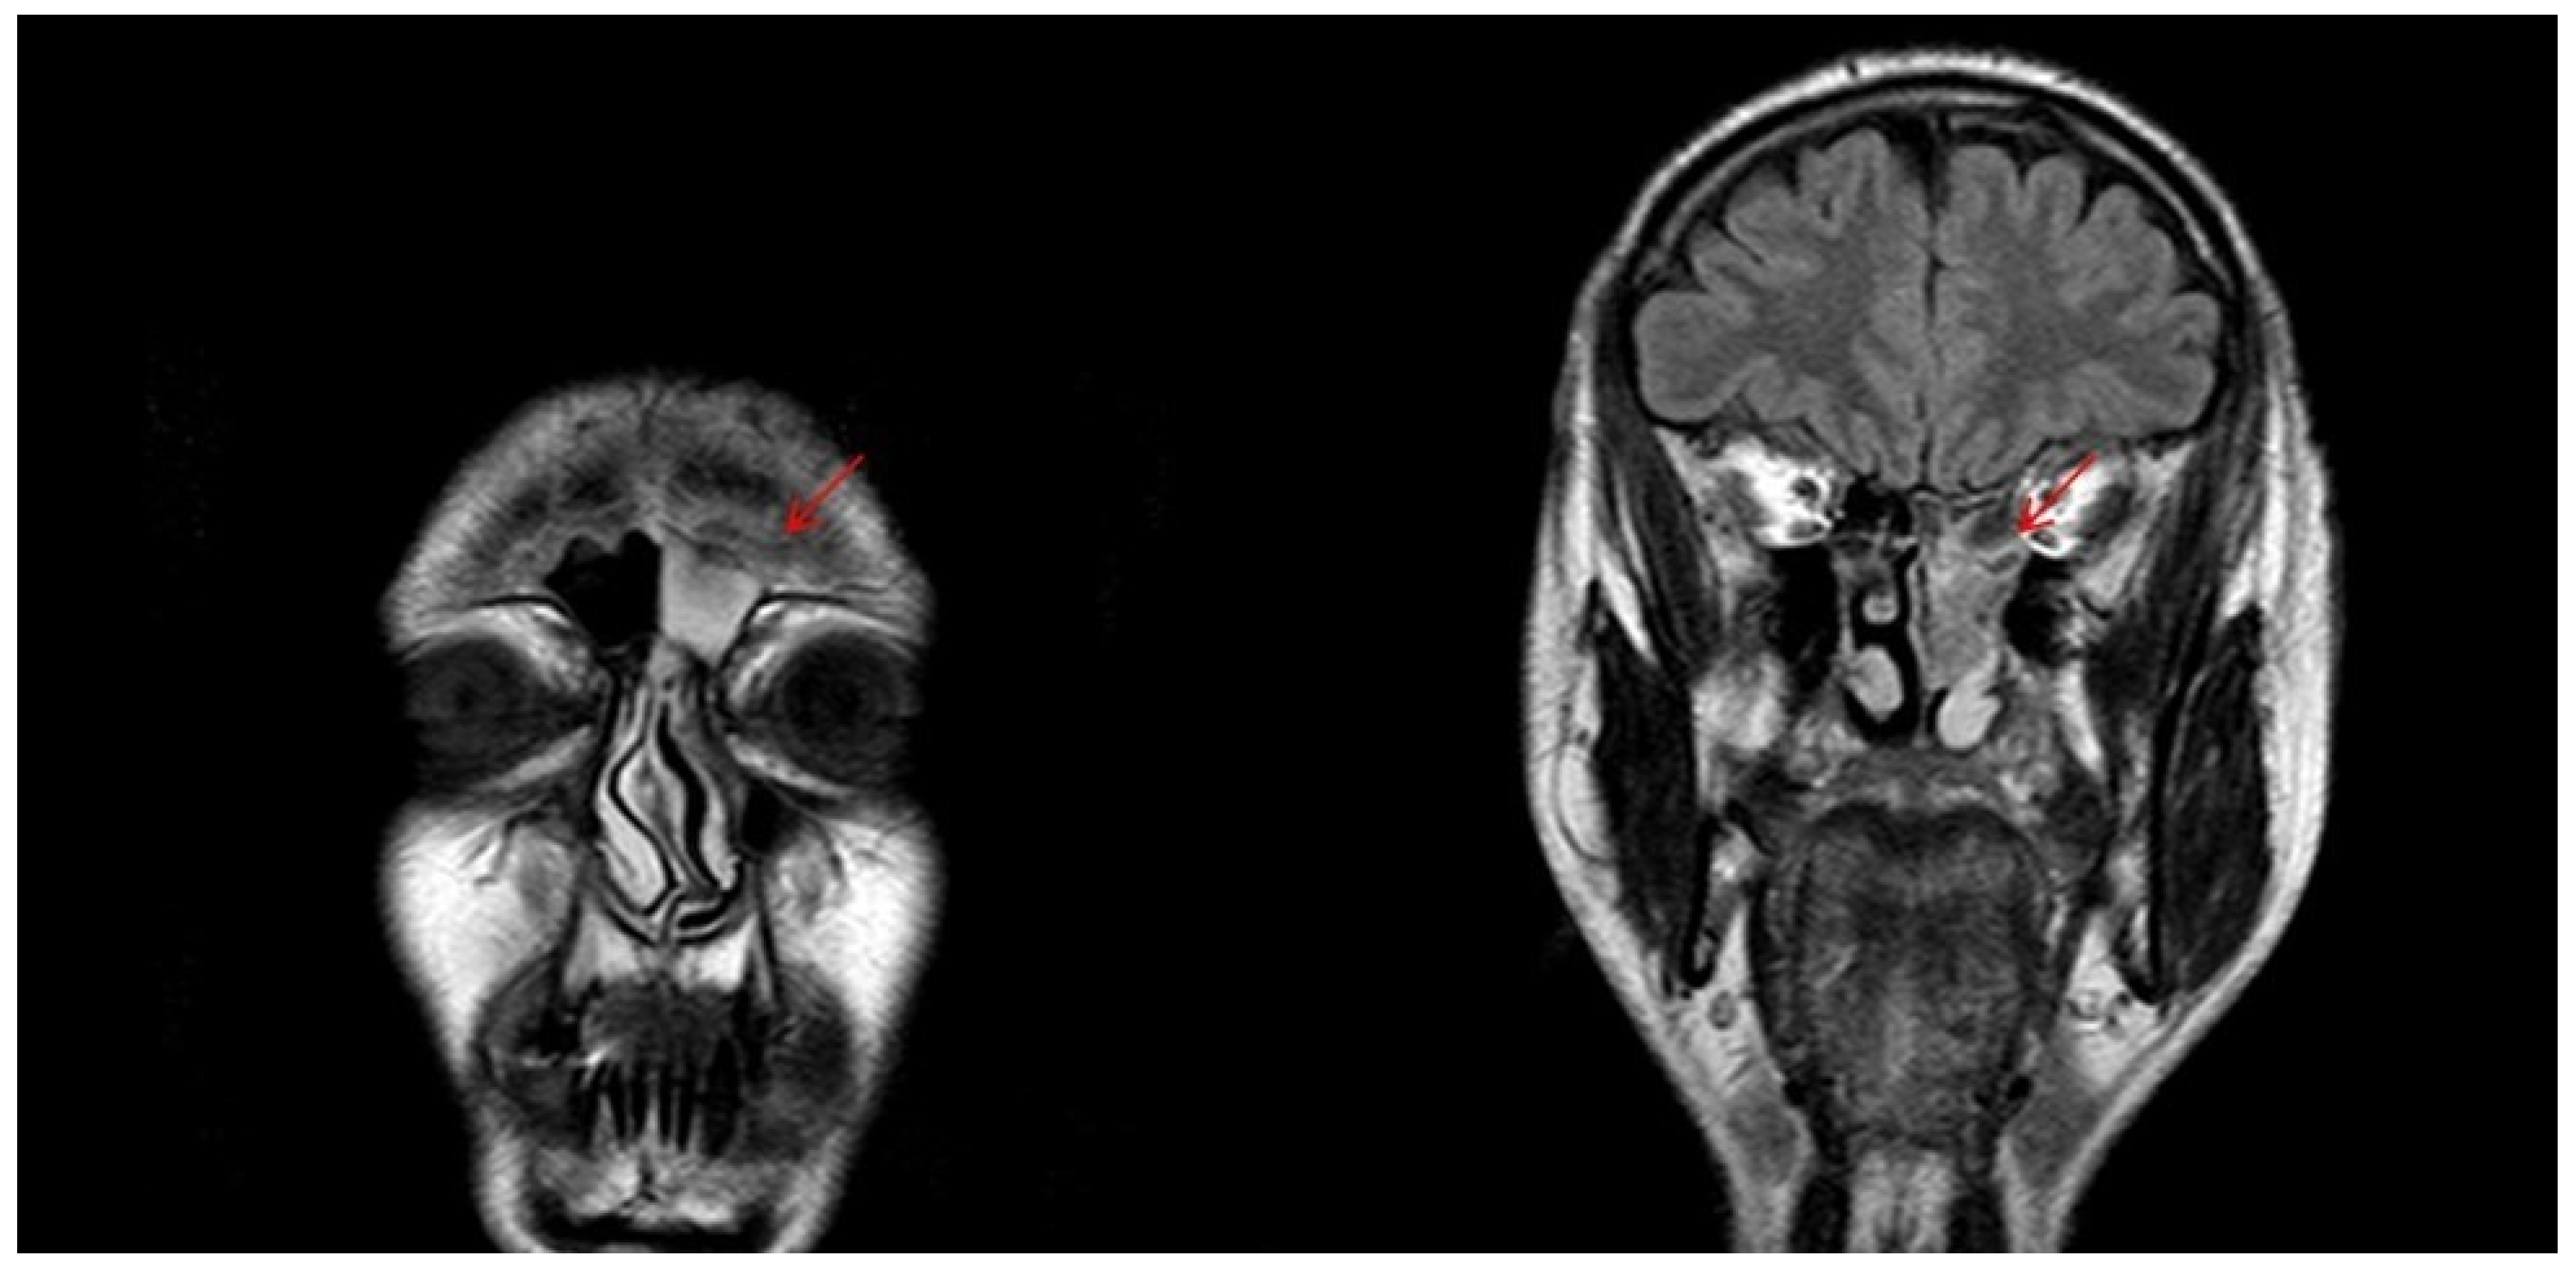

- Kawaguchi, M.; Kato, H.; Tomita, H.; Mizuta, K.; Aoki, M.; Hara, A.; Matsuo, M. Imaging Characteristics of Malignant Sinonasal Tumors. J. Clin. Med. 2017, 6, 116. [Google Scholar] [CrossRef]

- Sivalingam, J.; Sarawagi, R.; Raghuwanshi, S.; Yadav, P.K. Sinonasal Neoplasia – Clinicopathological Profile And Importance of Computed Tomography. J. Clin. Diagn. Res. 2015, 9, TC01–TC04. [Google Scholar] [CrossRef]